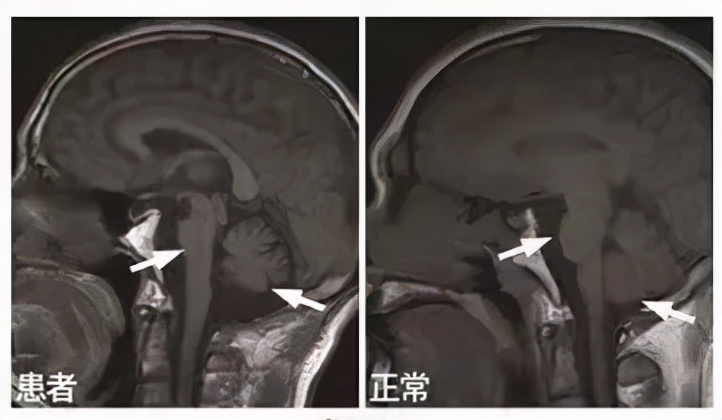

③运动症状发作3年内出现姿势不稳;④小脑功能障碍;⑤运动症状发作5年内出现吞咽困难;⑥MRI核磁表现壳核、小脑中脚、脑桥或小脑萎缩;⑦18F-FDG-PET(脱氧葡萄糖正电子发射计算机断层显像技术)表现为壳核、脑干或小脑低代谢。

②MRI核磁表现壳核、小脑中脚或脑桥萎缩;

图 |核磁提示脑桥、小脑明显萎缩